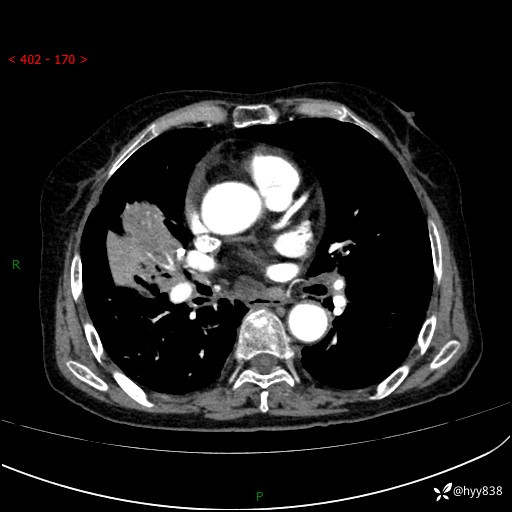

胸部CT增强(外院平扫)